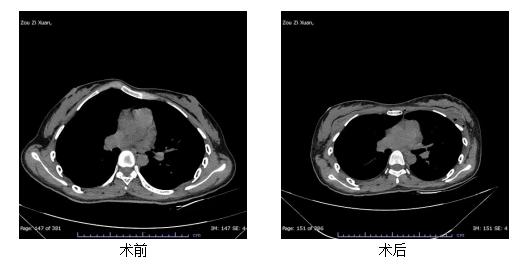

近日,91porn (湖北省中山91porn )胸外科(血管外科)收治了一位18岁的鸡胸患者。该患者因胸骨明显前凸,不仅运动时感到呼吸受限,更因外观问题长期承受着巨大的心理压力。科室团队为其成功实施了胸骨沉降手术,术后患者胸廓外观改善明显,呼吸功能有效恢复,困扰多年的心理负担也终于得以卸下。